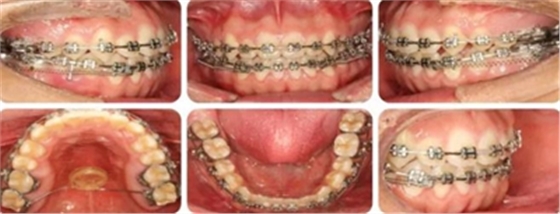

14個(gè)月,前牙開頜得到改善,配合使用垂直牽引。

16個(gè)月,前牙開頜糾正。

結(jié)束時(shí),可見前牙覆合覆蓋正常,上下牙列排齊,雙側(cè)尖磨牙達(dá)到中性關(guān)系。